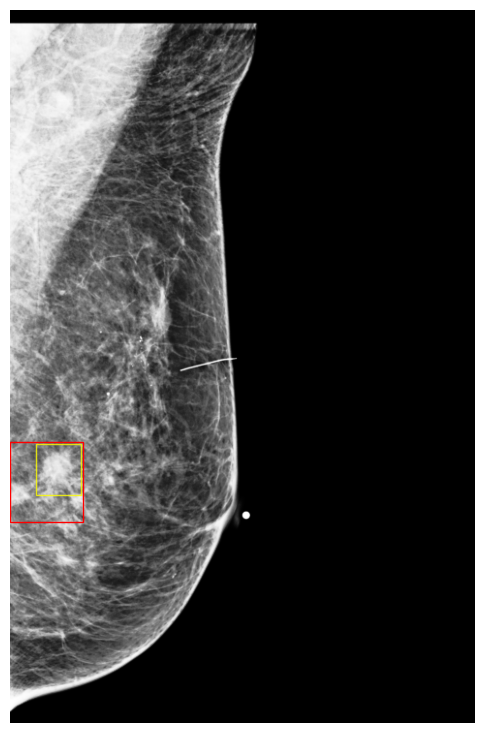

(Wu et al., 2019) contains digital screening mammography exams from patients screened at NYU Langone Health. Each exam includes a minimum of four images, each with a resolution of , covering two standard screening views: craniocaudal (CC) and mediolateral oblique (MLO), for both the left and right breasts. An example of a mammography exam is shown in Figure 4. The dataset is annotated with breast-level cancer labels indicating biopsy-confirmed benign or malignant findings. Moreover, the dataset also provides bounding box annotations, and class labels (benign or malignant) of each visible positive findings. The entire dataset contains breasts with malignant findings and breasts with benign findings. The dataset is divided into training (), validation () and test sets () ensuring a proportional distribution of benign and malignant cases across the subsets.

Cases Visualization on NYU Breast

Finally, to better understand how DETR models make predictions, we visualized a few exams along with their classification scores on NYU Breast dataset. Figures 9 and 10 show images in which the model assigned cancerous objects high malignant scores (scores ) and low scores (scores ), respectively. We observed that the model correctly localizes abnormal objects in all images. However, it tends to assign high scores to high-density masses featuring non-circumscribed, irregular, or indistinct borders, which are typically indicative of malignancy to the human eye. In contrast, the model usually assigns low scores to low-density masses with circumscribed borders, which can easily be confused with benign cases (Lee et al., 2018).